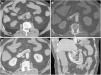

Fístula ilioentérica secundaria en un varón de 93 años, con antecedente de bypass aortobifemoral, que acude por presentar vómitos en posos de café y melenas. No se administra contraste intravenoso por disminución de la tasa de filtrado glomerular. Se representan cortes craneocaudales en el plano axial (A, B, C) del bypass aortobifemoral (punta de flecha) localizado en una disposición anterior a la aorta nativa (a). En la figura C se identifica gas intraluminal en la rama derecha del bypass (flecha) procedente del asa intestinal inmediatamente adyacente; se indica la arteria ilíaca nativa como referencia anatómica (i). La reconstrucción sagital (D) representa el nivel de los cortes.

Fístula aortoentérica secundaria en varón de 78 años con antecedente de bypass aortobifemoral y enfermedad ulcerosa péptica que acude por cuadro de hemorragia digestiva alta. La endoscopia reveló una ulceración de la pared intestinal con observación directa del material del bypass. Ante la estabilidad hemodinámica del paciente se decide valorar con tomografía computarizada. Fases arterial (A), portal (B) y reconstrucción MIP en el plano sagital (C). El bypass aortobifemoral se observa en íntimo contacto con el duodeno retroperitoneal presentando un manguito de partes blandas que rodea el bypass (*) y una burbuja de aire ectópico (punta de flecha) sin plano graso de separación. Aunque no se demuestra extravasación activa de CIV, la cirugía confirmó la presencia de FAE.